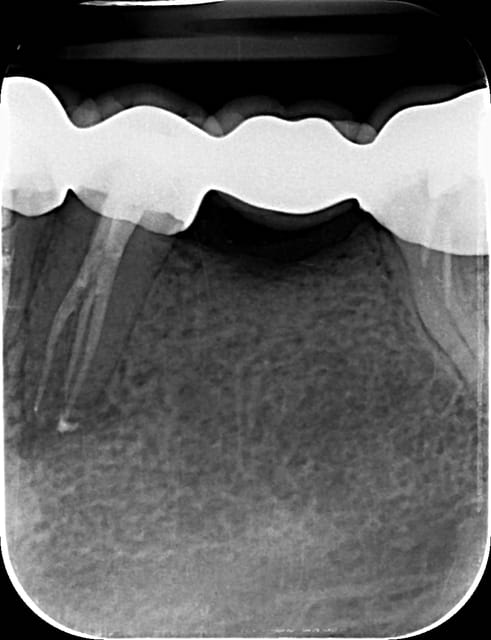

> 35 - MOD avec endodontic traitment e direct composite reconstruction

etait il indispensable de faire le traitement endodontique dans ce cas ?

@l adan - oui, parque la indicateur de la carie (Sable Seek Ultradent ) montre une zone affectée près de la cambre du nerf.